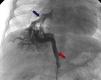

Com um mês realiza AngioTAC, que revelou MAPCA única a emergir do tronco celíaco para o pulmão direito, drenando na veia pulmonar inferior direita (Figura 1).

Realizou cateterismo diagnóstico e terapêutico aos cinco meses: pressões sistémicas e pulmonares normais; angiografia na artéria pulmonar: ramos de bom calibre e retorno venoso normal (perfusão mista do campo inferior direito vinda da artéria pulmonar e MAPCA) (Figura 2); angiografia na aorta: colateral larga (7 mm), origem no tronco celíaco, dirigindo‐se para o pulmão inferior direito (Figura 3). Decidida embolização da colateral com Amplatzer (10‐7 PLUG II), ficando com shunt residual (Figura 4).